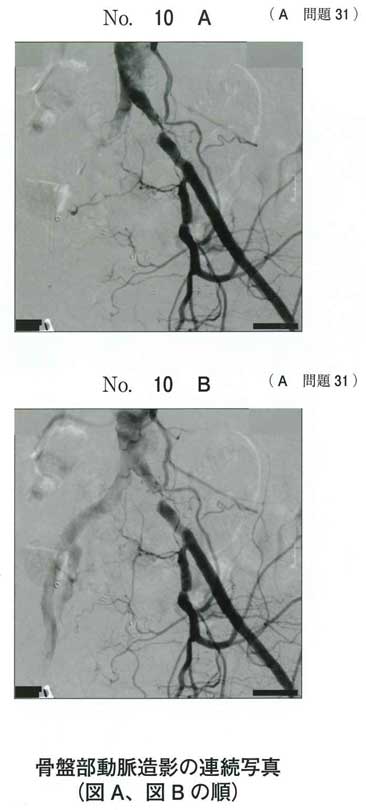

イヤーノートでASOについて調べました。

dのようです。

ワルファリンは抗凝固薬ですが、ASOではアスピリンなどの抗血小板薬を用います。

動脈硬化は抗血小板。さすがに常識か。